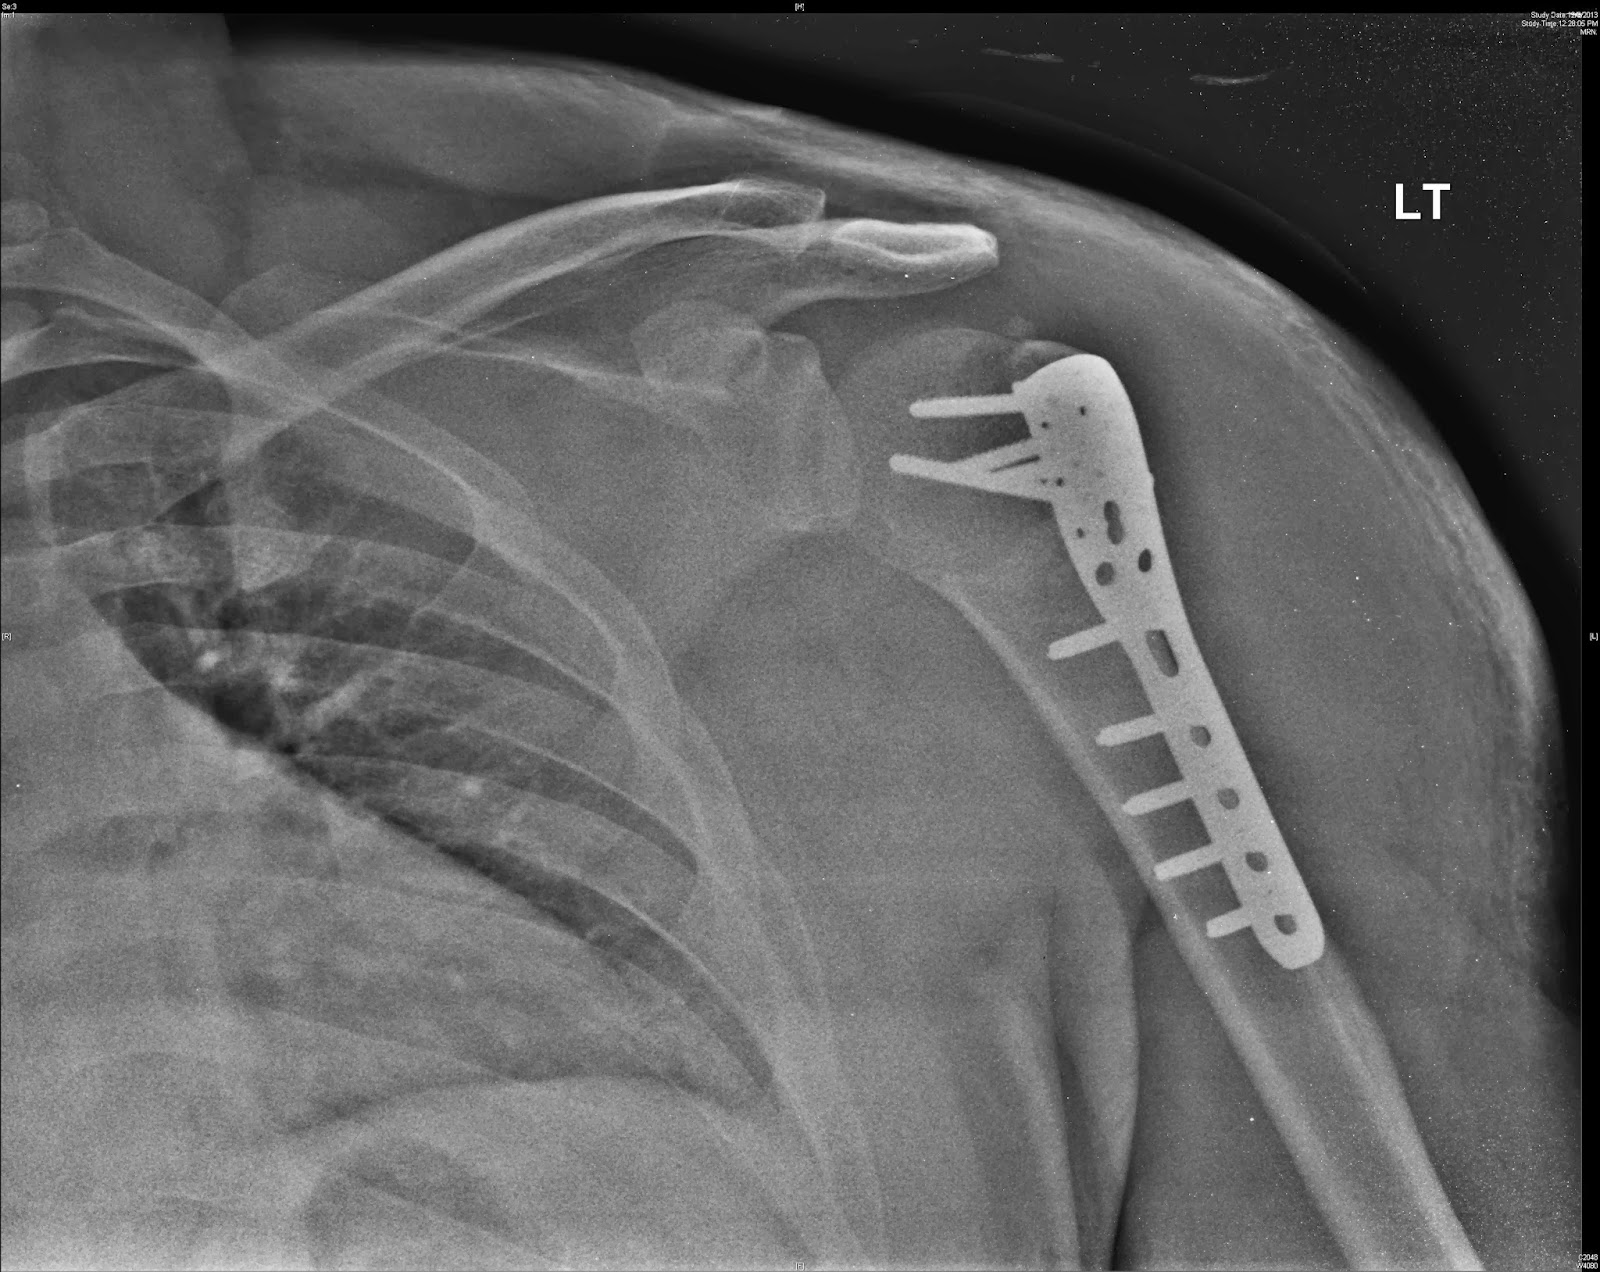

From www.alamy.com

Shoulder x ray spiral fracture of humerus Stock Photo Alamy Spiral Fracture Humerus Baseball baseball player who underwent successful ld/tm repair for grade iv tear and subsequently sustained a spiral humeral. the direction of the torque was consistent with the external rotation spiral fractures of the humerus noted to occur in throwers. ogawa and yoshida 11 reported the largest series of thrower’s fractures to. Spiral Fracture Humerus Baseball.